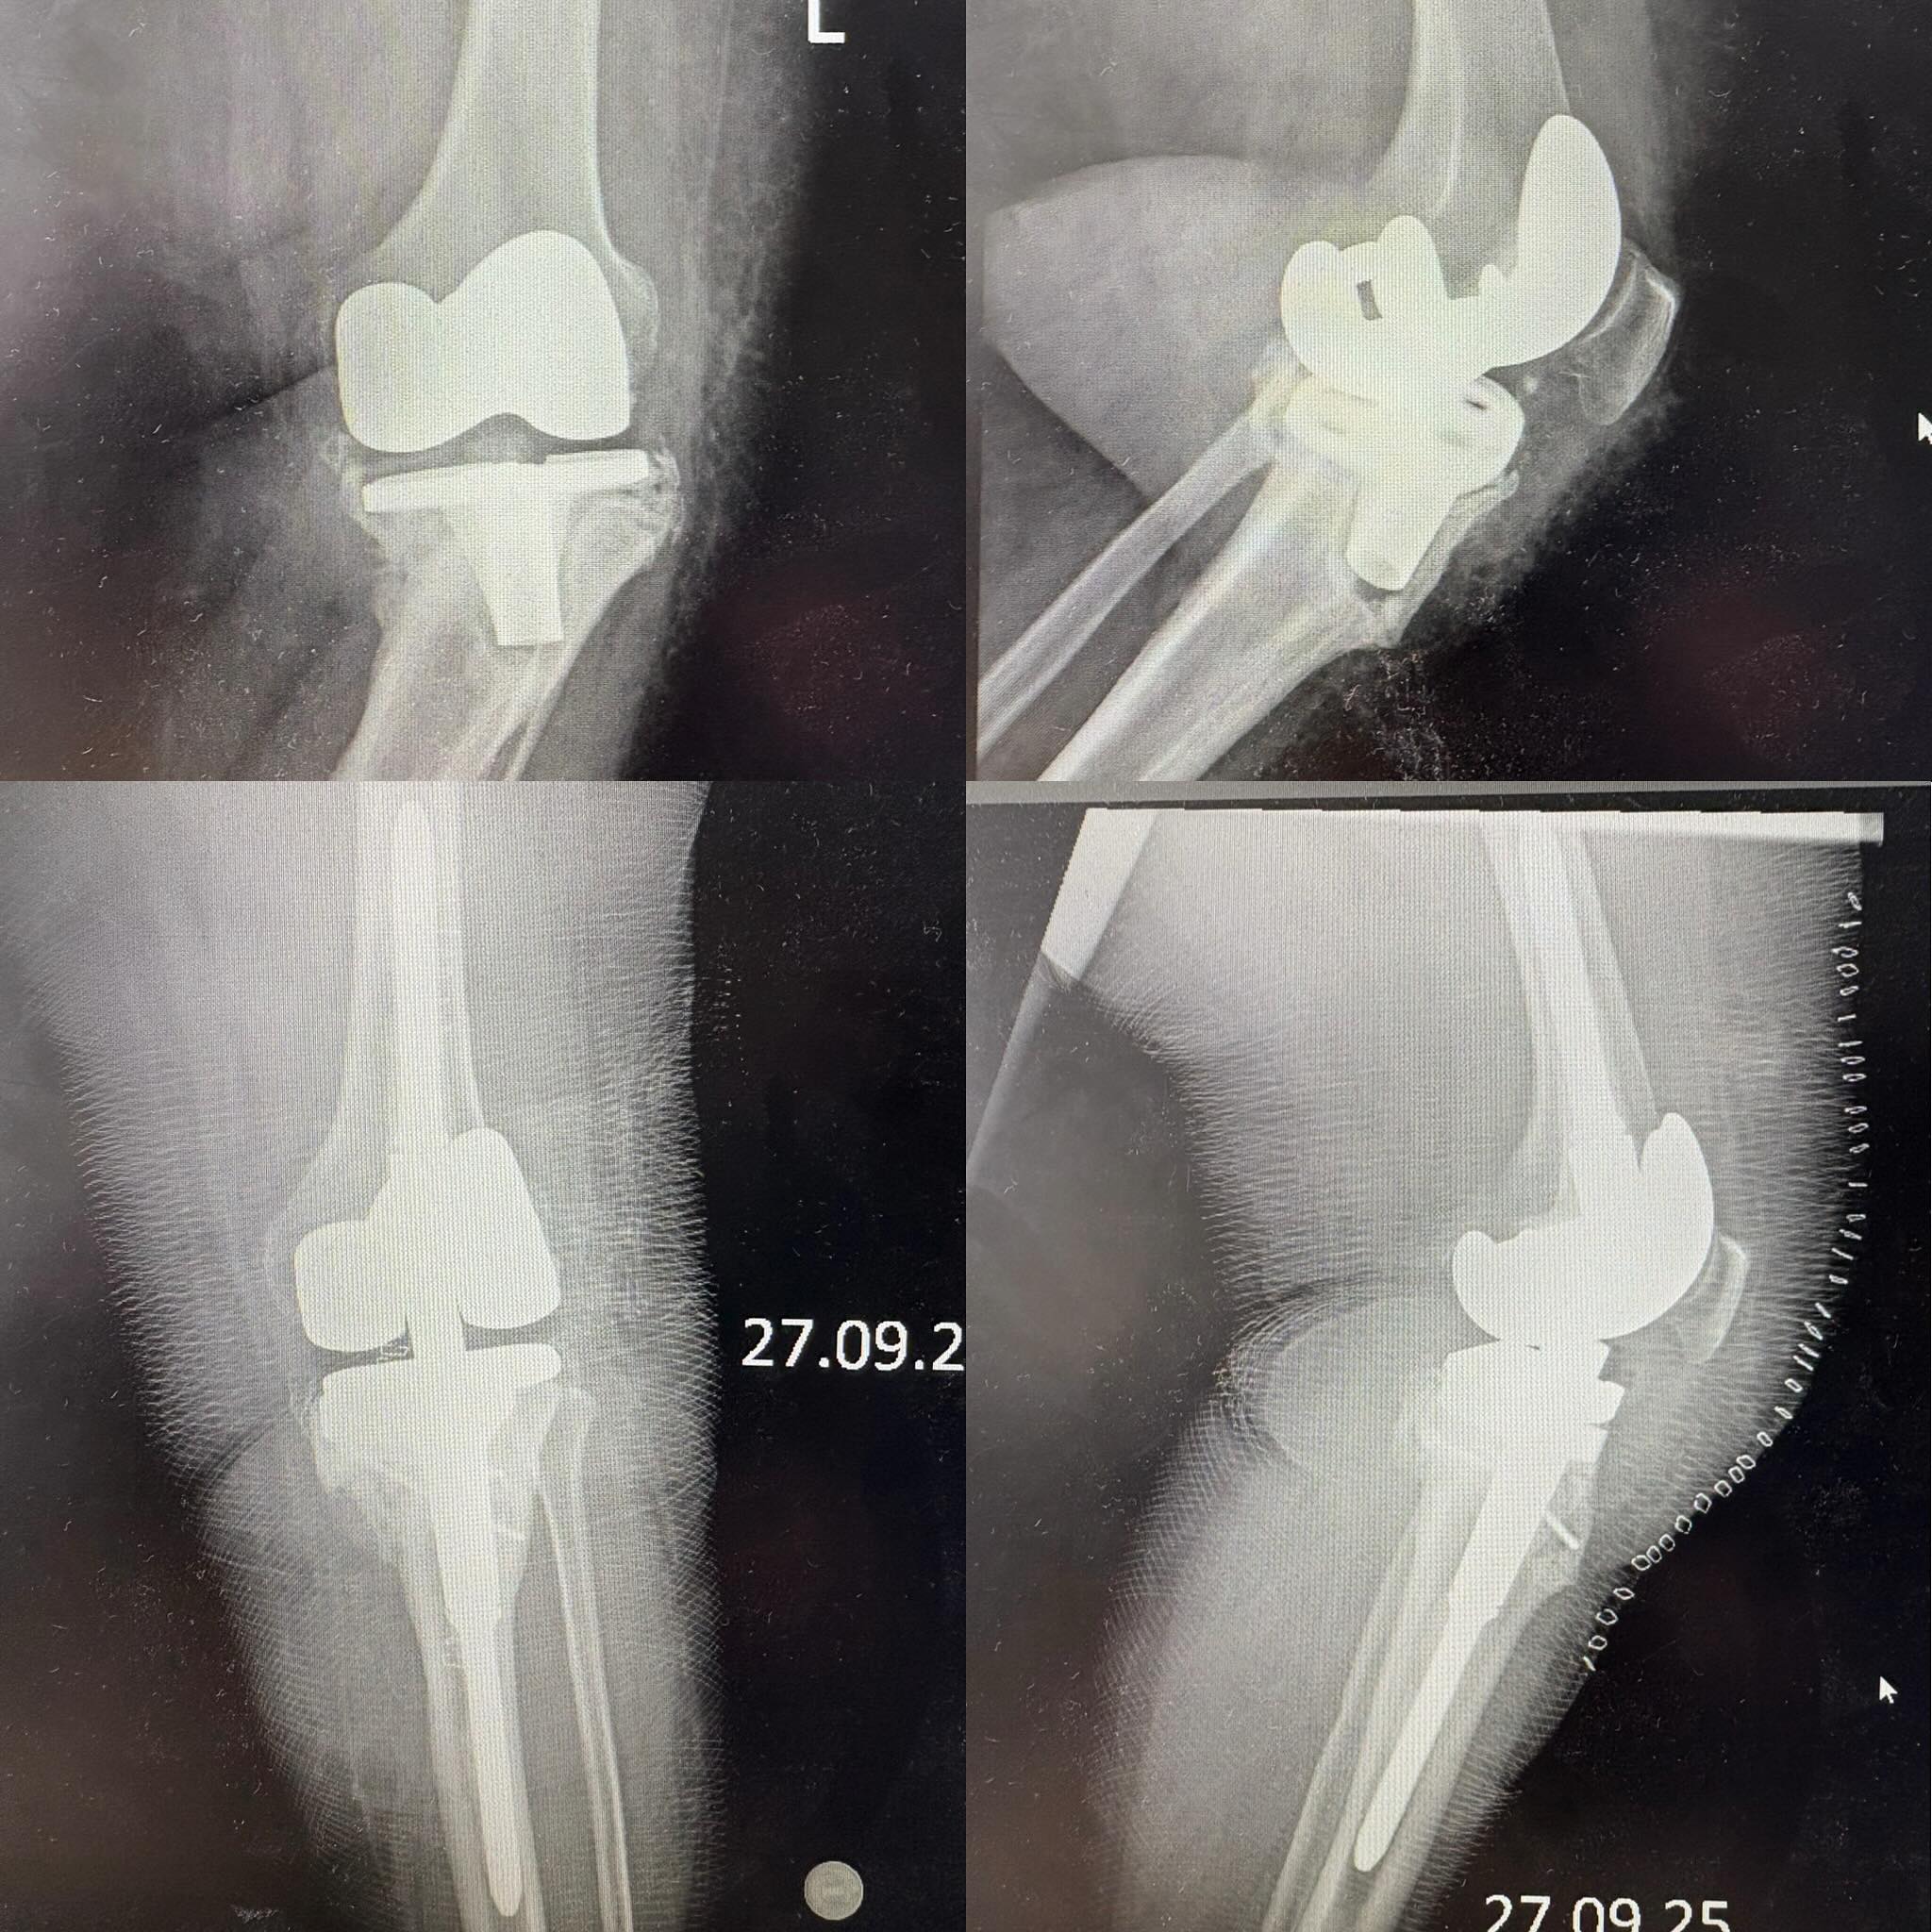

Ревизионное эндопротезирование

Ревизионное эндопротезирование (т.е. повторное, с заменой эндопротеза) является довольно сложной операцией, гораздо более сложной по сравнению с первичным эндопротезированием.Она требует специального подхода, учёта технических нюансов, а также знаний, опыта, подготовки и соответствующего оснащения.Кроме того, операция недешёвая, при этом очень нужная и в большинстве случаев – безальтернативная для пациента.Поэтому данное направление, по мнению Тараса Григорьевича – именно то, на что в ближайшем будущем должна быть направлена государственная социальная поддержка в медицинской сфере.